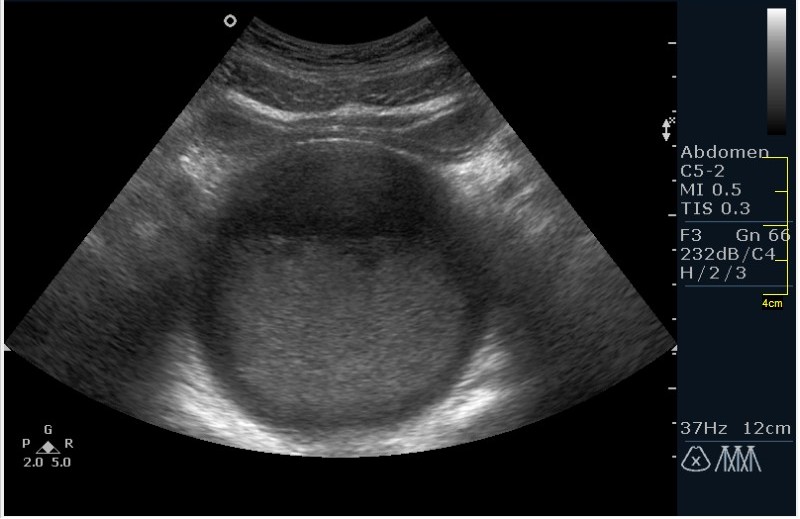

Девочка 12 лет; жалобы на частое мочеиспускание; тупые, тянущие боли в малом тазу. Менструацию отрицает. УЗИ малого таза, все сонограммы выполнены по средней линии, в поперечной и сагитальной проекциях.

Гематокольпос при заращении девственной плевы. Менархе. Врожденная аномалия половых органов.